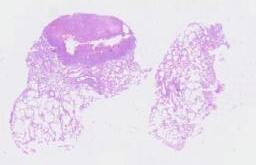

临床资料: 男性,45岁,CT发现双肺多发结节,较大者位于右肺中叶外侧段,直径约14mm。